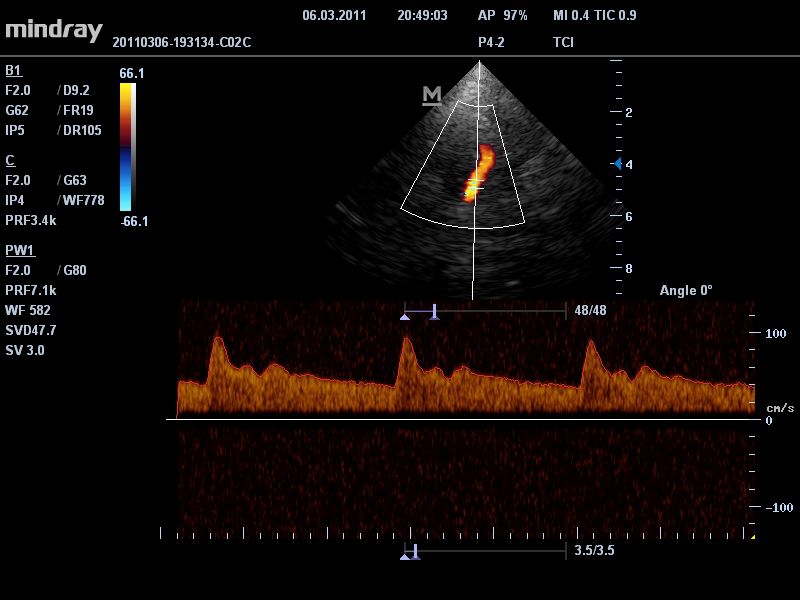

Импульсно-волновой допплер:

Да

• Режимы сканирования: B/M/CFM/PDI/Направленный PDI/PW, HPRF, Тканевая гармоника, М- и цветной М-режим.